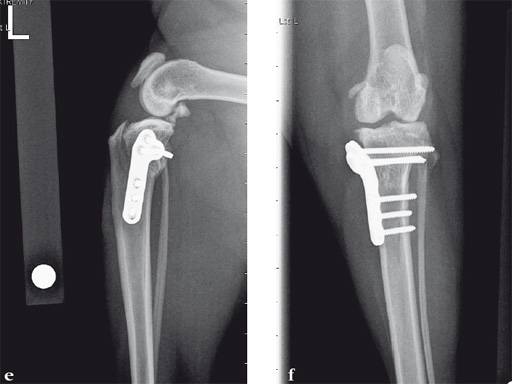

An 11-year-old female, spayed, 13.6 kg cocker spaniel had a complete tear of the left cranial cruciate ligament. A 2.4 mm TPLO plate was perfect for this dog due to the excessive slope of the tibial plateau (30) and the size of the dog. Three 2.4 mm locking screws were used proximally and three 2.4 mm cortical screws were used distally. The contour of this plate matches the contour of the bone almost perfectly. The plate is also designed to optimize the angle of the proximal screws so that they engage the most dense and thickest bone and avoids penetration of the stifle joint.

A 10-year-old female, spayed, 6.0 kg cat had a partial tear of the left cranial cruciate ligament, meniscal mineralization, and a medial meniscal tear. The cat was treated with a partial meniscectomy and TPLO . A 2.0 mm TPLO plate was perfect for this cat due to the slope of the tibial plateau (25) and the size of the cat. Three 2.0 mm locking screws were used proximally and three 2.0 mm cortex screws were used distally. The contour of this plate does not perfectly match the contour of the proximal tibia, but use of locking screws in this segment avoids any potential angulation of the segments as the screws are tightened. The cat healed uneventfully and returned to normal function.